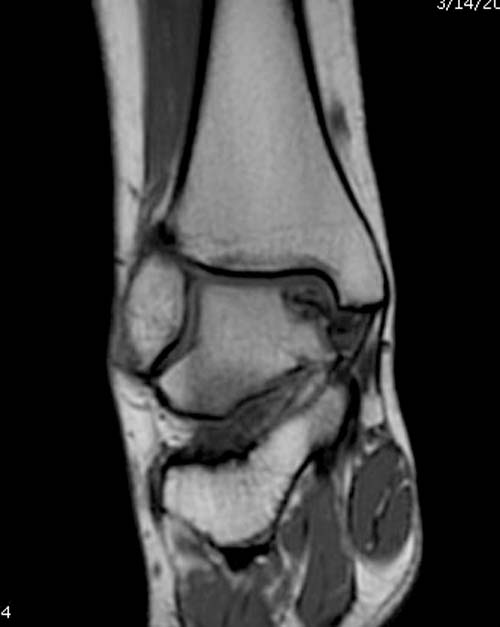

Доброго времени суток, уважаемые коллеги. Прошу помочь определиться с тактикой лечения. Пациентка 40 лет, в течение последних 8-9 мес. беспокоила боль в левом голеностопном суставе после значительной физической нагрузки (по роду деятельности вынуждена проходить в день не менее 15 км). Факт травмы отрицает. Лечилась самостоятельно, мазями и приемом НПВП. В последнее время боль стала возникать после умеренной нагрузки, присоединились отек и хромота. Прием НПВП и ограничение нагрузки до уровня бытовой болевой и отечный синдром купируют. Обратилась к нам, выявлены изменения таранной и пяточной кости, представленные на КТ. Вопрос: единственным ли выходом является артродез или можно обойтись менее радикальным вмешательством? Смущает невыраженная клиника и молодой возраст пациентки... Будем рады любой помощи со стороны уважаемого сообщества. А. Баженов, г. Екатеринбург

Разбираемый случай не имеет ничего общего с классическим Аваскулярным Некрозом Таранной кости. Здесь так назывемый (osteochondral defect) или osteochondritis dissecans (OCD) таранной кости, при котором патология локализуется в медиально-верхнем нагрузочном отделе. В основном OCD

встречается после хронической травмы, но бывают случаи врожденного генеза, которые обнаруживаются при случайных исследованиях.

Симптоматология OCD выражается слабым отеком, а более сильные боли наступают после физической нагрузки. В отличие от АВН тарана, когда боли постоянные, а при OCD боли изчезают после отдыха. В начальных стадиях

на рентгенограммах не всегда заметны склерозные участки, и поэтому в большинстве диагноз устанавливается поздно. Приход КТ и МРТ улучшил диагностику, и в срезах внутри кисты можно увидеть жидкость, но это не означает проявление симптоматологии. Симптомы проявляются с момента образования внутрисуставных краевых фрагментаций!